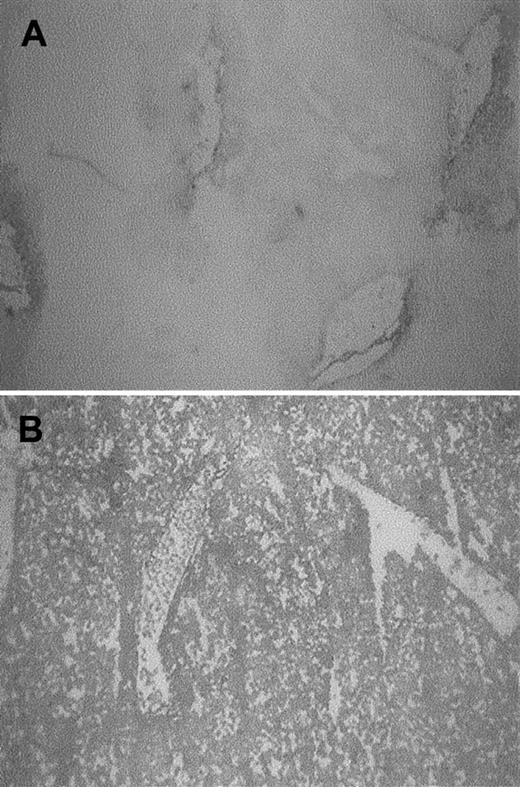

Sections of pancreas from mice exposed to heme also showed severe alterations when compared to control mice treated with saline (Figure6). In the heme-treated animals, the presence of inflammatory hallmarks such as interstitial edema and cellular infiltration could easily be observed, corroborating our findings obtained in the biodistribution studies with the radiolabeled liposomes and leukocytes.

Effect of heme on inflammatory changes in the pancreas.

Sections of the pancreas of mice treated for 24 hours with saline (A,B) or heme (750 μM) (C,D) were stained with H&E (original magnification, × 40 [A,C] or × 400 [B, D]). Exposure to heme resulted in a variety of inflammatory changes in the pancreas, as illustrated by leukocyte influx and interstitial edema.